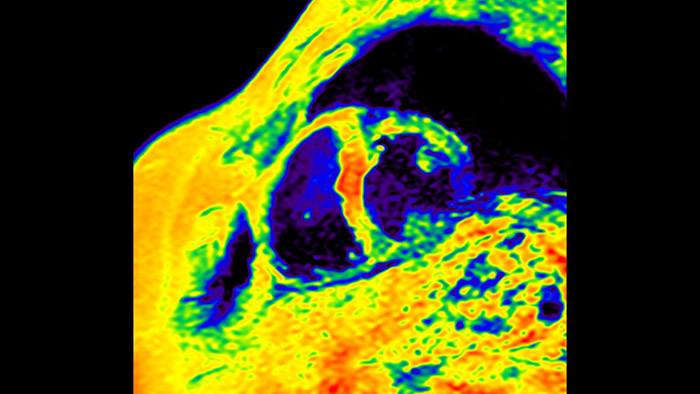

Today's diagnostics often cannot detect heart dysfunction until symptoms occur. MyoStrain utilises segmental strain to measure 48 segments of the heart and provides physicians with a unique diagnostic tool to help identify regional dysfunction before the heart as a whole is affected.

IntelliSpace Portal MR Caas5,6 Strain7 assists in patient diagnosis and monitoring by providing global strain parameters such as global longitudinal strain (GLS), global circumferential strain (GCS), and global radial strain (GRS), using short and long axis MR images, as well as describing the myocardium deformation- such as shortening, thickening, and lengthening during the cardiac cycle.